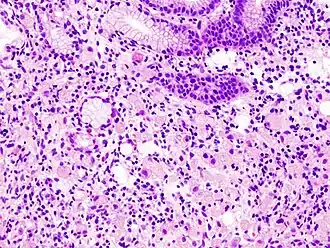

High magnification micrograph showing signet ring cells, with clear cytoplasm, in metastatic breast carcinoma. H&E stain. -

The name of the cell comes from its appearance; signet ring cells resemble signet rings. They contain a large amount of mucin, which pushes the nucleus to the cell periphery. The pool of mucin in a signet ring cell mimics the appearance of a finger hole and the nucleus mimics the appearance of the face of the ring in profile.